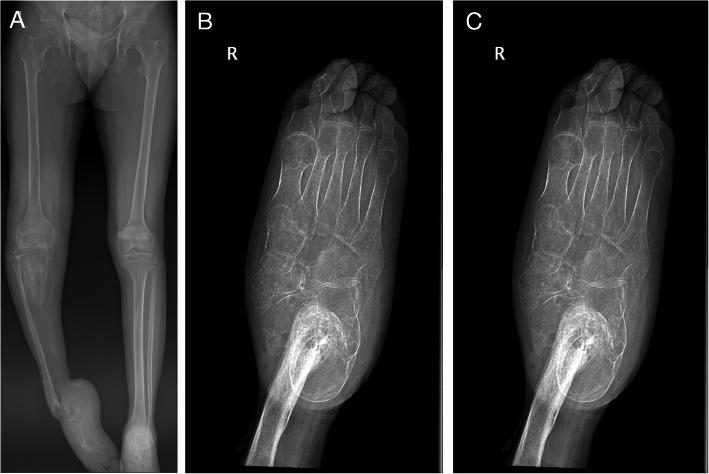

We present a case of an immense unprecedented tibial bone lengthening of 33.5 cm. The management of chronic osteomyelitis of the right tibia with subtotal tibial bone defect, talus defect and equinus ankle deformity. We demonstrate limb reconstruction by distraction osteogenesis and correction of ankle deformity with the Ilizarov technique. Limb salvage was preferred as an alternative to amputation to restore basic limb function.

A 16-year-old male patient fell and injured his right lower leg. He attempted to treat the symptoms with traditional home remedies. During 15 months of self-treating, he developed osteomyelitis of the right tibia and had lost function in his foot. Radiology revealed immense bone defect of the right tibia, including talus bone defect and equinus deformity of the calcaneus. The patient's right tibia was non weight-bearing, had drainage sinus just below his knee and a large scar anteriorly along the entire length of the tibia.

Upon completion of treatment, the patient was able to avoid amputation of his leg with partially restored function for weight-bearing. He carried himself without assistance after 3 years of lost function in his right leg. Tibial bone distraction osteogenesis of 33.5 cm was done after 90% of the tibial length was defected. To the best of our best knowledge, this case is one of a kind to achieve distraction of tibial bone to such length.